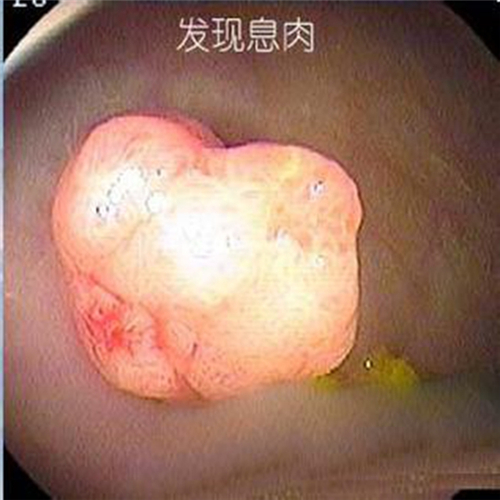

直腸息肉圖片

直腸息肉早期